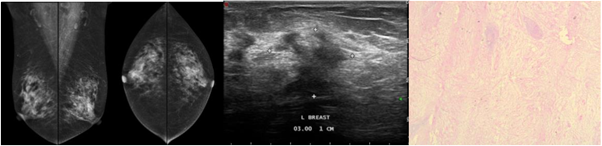

A 59-year-old female presented with right breast lump since 2 months before. There was history of DM on insulin treatment. Physical examination revealed a hard, indistinct border, and low movable mass in the upper outer quadrant of the right breast with mild tenderness. Mammography showed asymmetrical density in right upper outer quadrant, without any microcalcification. US showed irregular solid masses, hypoechoic, with angular margin and posterior shadowing in upper lateral quadrant, interconnecting with total sized >50mm with no vascularization inside the mass, suggesting a malignancy. Incisional biopsy result consistent with DMP (Figure 1).

Figure 1 Mammography, US, and histopathologic findings of a 59-year-old female presented with right breast lump turned out to be DMP.